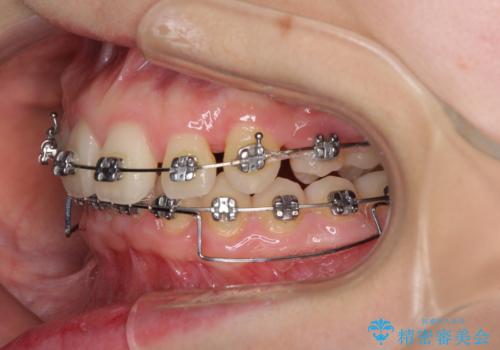

- 矯正装置

- メタルブラケット

奥歯の咬み合わせがなかなか定まらず、スペースが閉じるまでに時間がかかりましたが、最終的には正中を合わせることもできました。